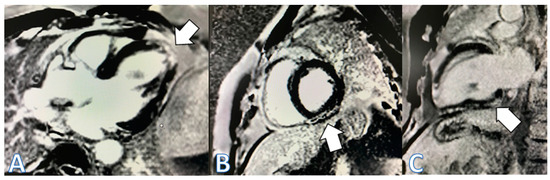

| CMR at hospitalization | LGE of both pericardial leaves and foci of late subepicardial enhancement on the basal inferolateral, lateral, and inferior walls | LGE at the level of the pericardial leaves and a basal inferolateral subepicardial focus | Edema and LGE in the lower-middle, inferolateral, and anterolateral segments | Edema and LGE at the anterolateral, basal-mid inferolateral and basal inferior segments, and intramyocardial in the mid-inferoseptal and apex segments |

| Control CMR at 3 months | Persistence of LGE on the inferolateral wall | Disappearance of LGE | - | - |

| Control CMR at 6–9 months | Persistence of LGE on the inferolateral wall | - | LGE in the inferolateral and anterolateral walls | LGE intramyocardial and subepicardial at inferolateral, anterolateral, and inferoseptal walls (reduced extent) |